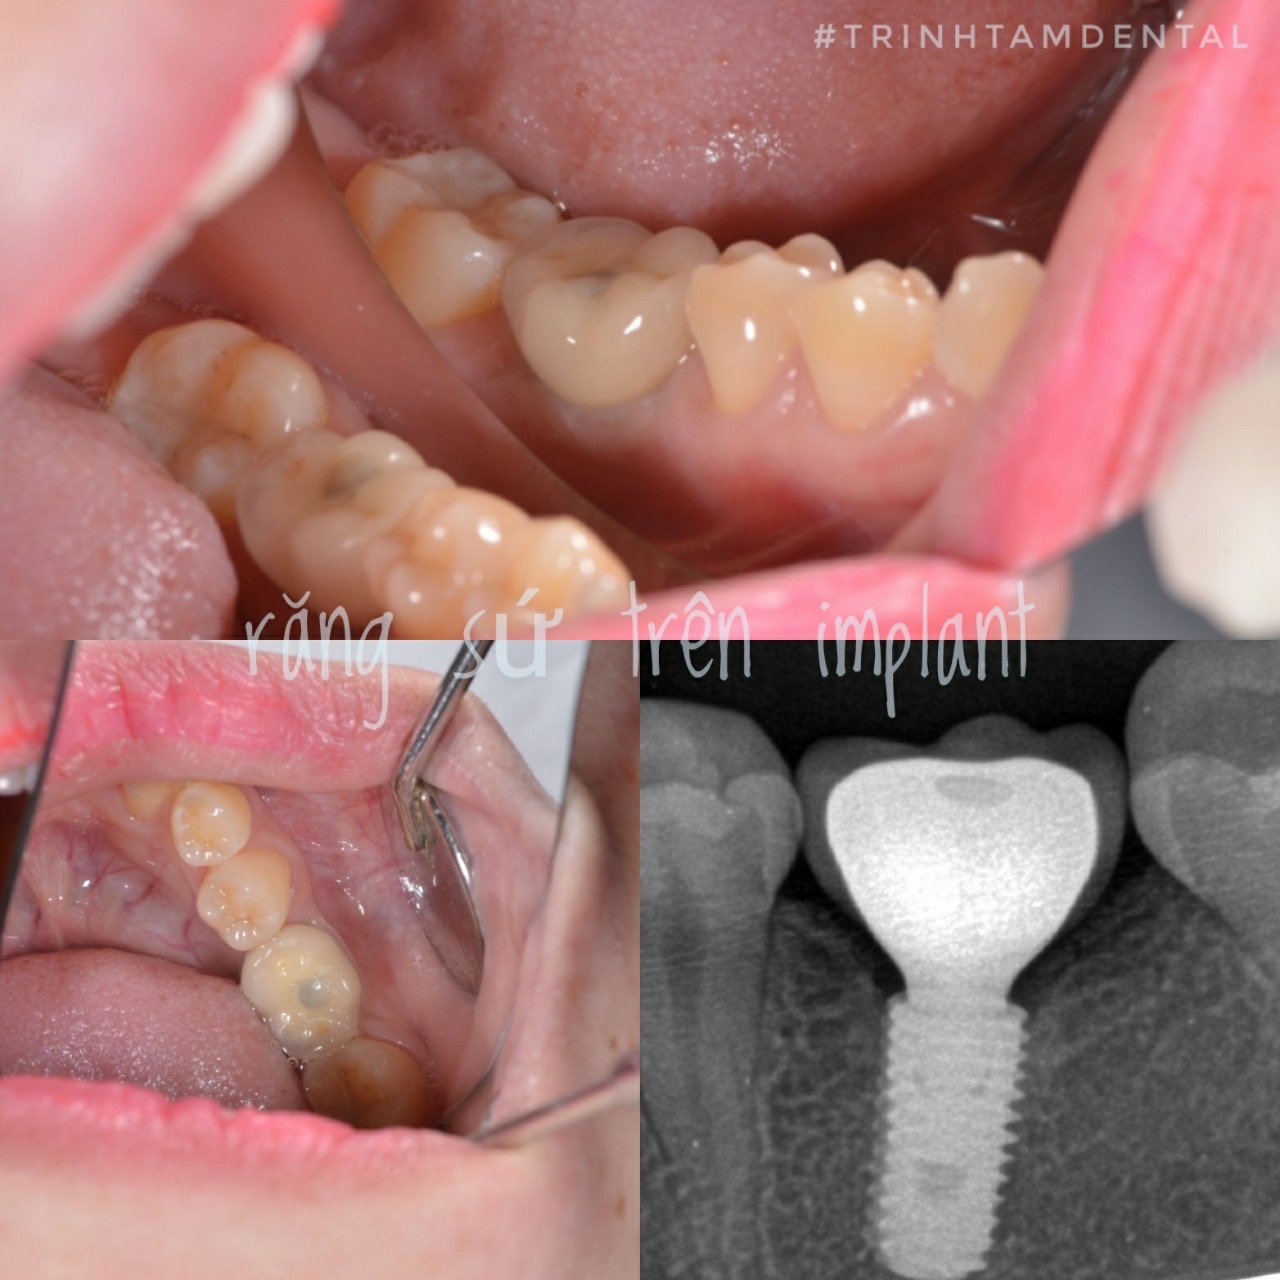

5 Lợi ích của cấy ghép Implant hay chân răng nhân tạo!

Cấy ghép Implant/chân răng nhân taọ là điều trị ngày càng phổ biến đối với những trường hợp mất răng do bệnh sâu răng, nha chu… Chúng ta hãy cùng tìm hiểu những lợi ích của điều trị này qua bài viết dưới đây.

Hình dạng Implant được thiết kế giống với chân răng tự nhiên. Vật liệu Titan sử dụng để chế tạo implant có khả năng tích hợp cứng chắc với xương hàm. Tuy có sự khác biệt nhỏ về mặt sinh học nhưng Implant cho cảm giác ăn nhai như răng thật.

Việc hạn chế tiêu xương hàm nhờ cấy ghép Implant sẽ giúp mô mềm ngoài mặt ít thay đổi so với trước khi mất răng. Thêm vào đó, hình dáng răng trên Implant rất giống với răng tự nhiên. Từ đó, tăng sự tụ tin và tạo thẩm mỹ nụ cười cho bệnh nhân.